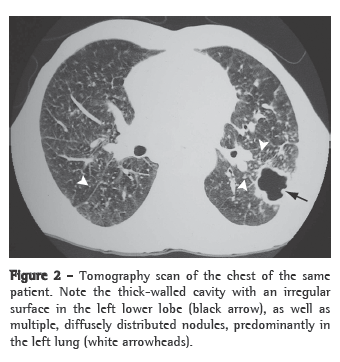

Patterns suggestive of silicotuberculosis have also been recognized on chest CT scans. The principal findings consistent with active tuberculosis superimposed on silicosis are thick-walled cavities (Figure 2), consolidations, images presenting a tree-in-bud pattern, nodular image asymmetry, and rapid disease progression.(26,28,29).